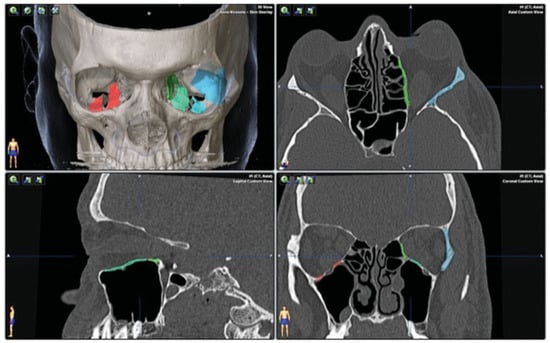

DICOM data from the CT study were imported into the planning software (iPlan CMF 3.0 BrainLab, Brainlab Inc., Westchester, IL) for preoperative planning. For each wall involved, the planned resection sites were indicated using different colors (Figure 2). A one-wall (orbital floor) decompression was planned on the right side and a three-wall decompression (lateral wall, floor, and medial wall) was planned for the left side.

Similar to the first case, DICOM data from the CT study were utilized to plan a two-wall (lateral wall and orbital floor) decompression on the right side and a three-wall decompression (lateral wall, floor, and medial wall) on the left side (Figure 8).

Figure 2. Axial, coronal, and sagittal views with 3D reconstruction for patient 1, showing the preoperative plan. Areas of planned decompression are highlighted in color.

Figure 8. Axial, coronal, and sagittal views with 3D reconstruction for patient 2, showing the preoperative plan for the left-sided, three-wall orbital decompression surgery.